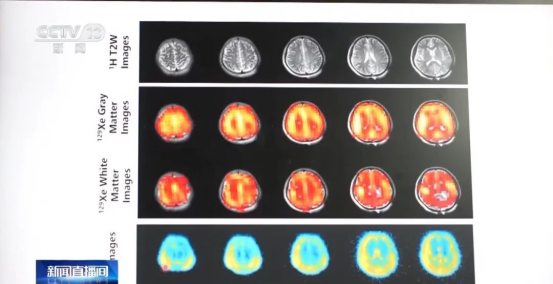

通过多核磁共振成像技术获得的医学影像,不同的颜色代表不同的人体元素,能清晰地反映氢、钠等元素在脑部分布聚集的状况。

中国科学院精密测量科学与技术创新研究院研究员周欣介绍说,“人体内有60多种元素,除了氢之外,现在还能探测到活体的钠和磷,多了两种元素,这就好比以前80年代我们看照片都是黑白照片,现在相当于‘多核’就指的是多种原子核,通俗一点就相当于是以后的磁共振是彩色的磁共振。”

周欣表示,多核磁共振成像技术能够反映出我们人体内更精细的信息——结构信息、功能信息、代谢信息。这三个方面层次的信息,为人体健康,包括疾病的诊断、治疗提供更全面的可视化的工具。能够直接看到患者脑部、心脏里面钠和磷的代谢,哪一个元素的代谢出了问题,哪个通路会有问题,能够为精准医学提供全新的仪器和技术。